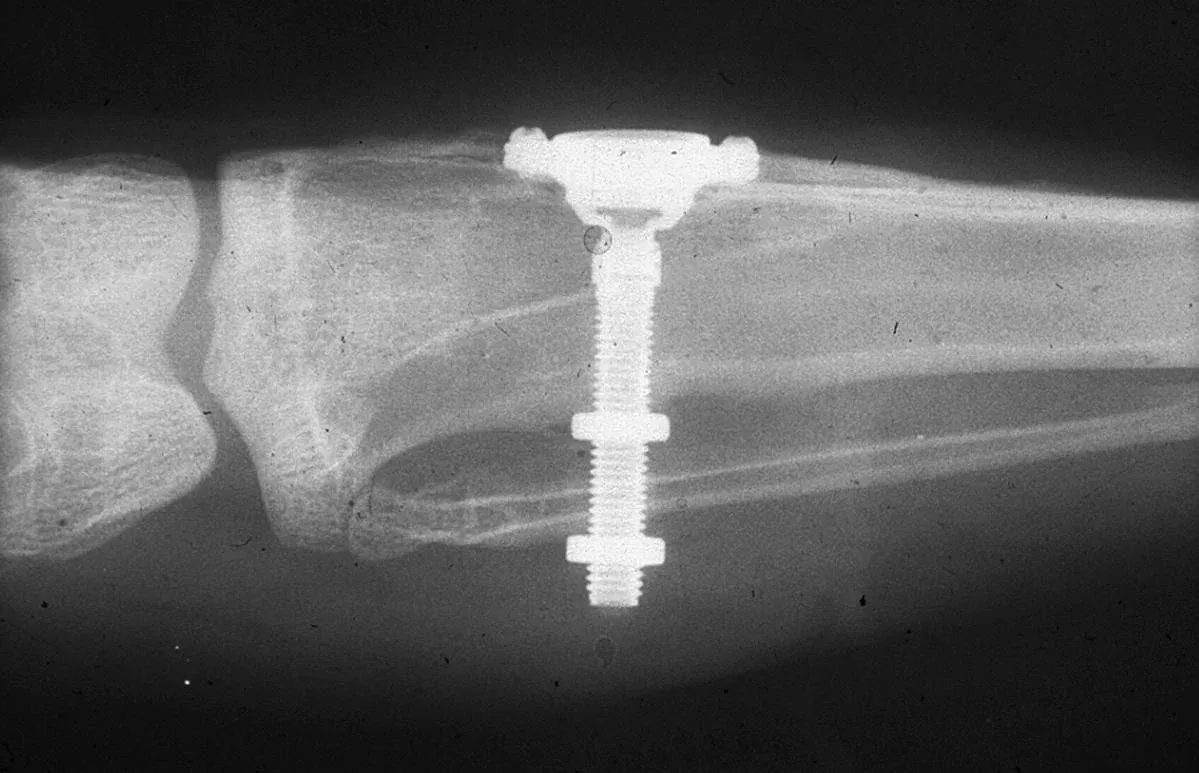

Radiografia originale di Brånemark: camera ottica in titanio nella fibula di un coniglio, 1952.

La radiografia originale di Brånemark — camera ottica in titanio nella fibula del coniglio. Per-Ingvar Brånemark, CC BY-SA 3.0, Wikimedia Commons.